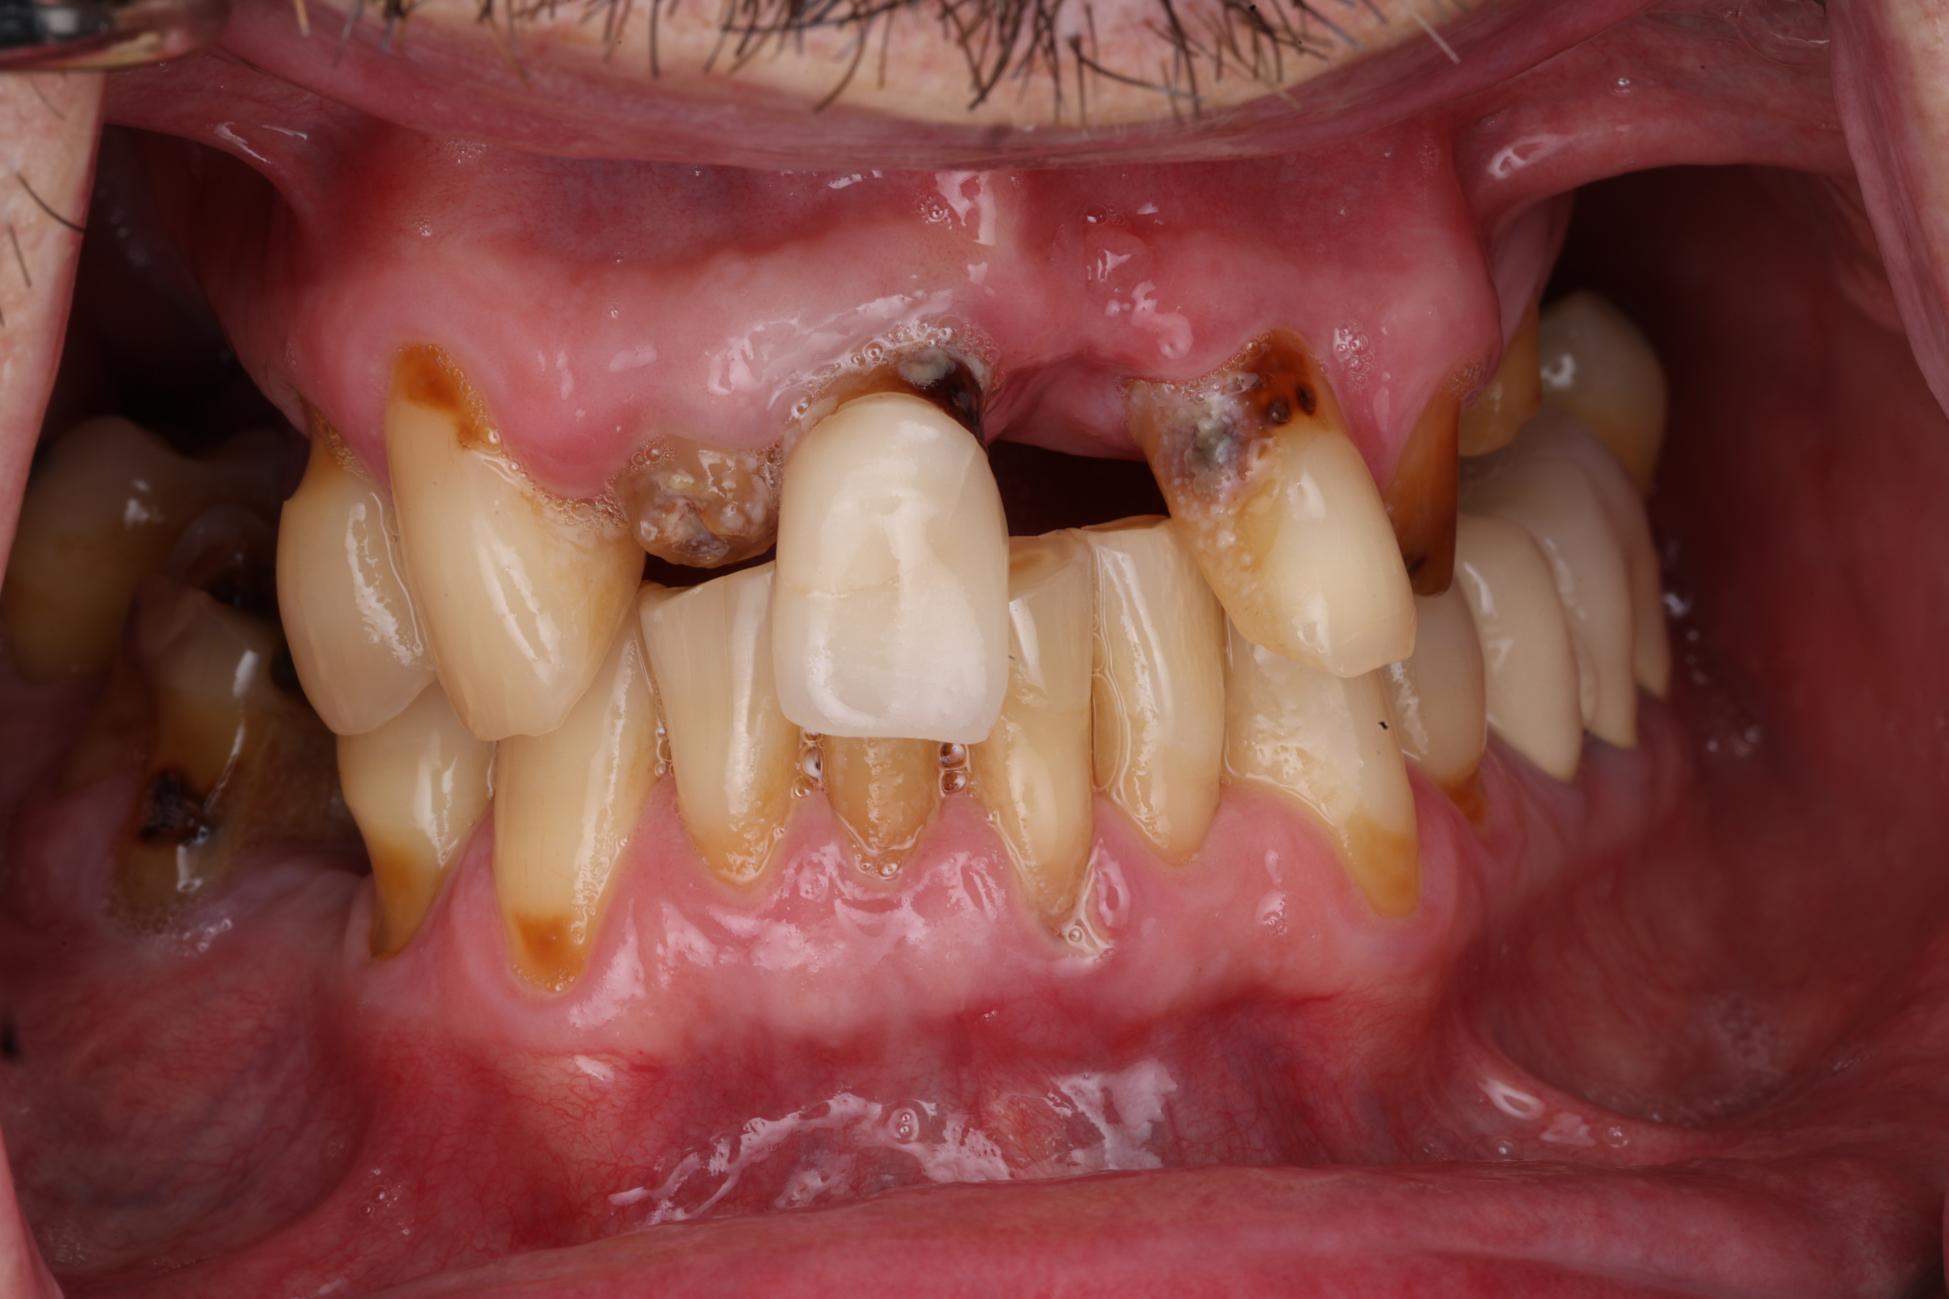

Full Arch Implant Therapy

Before After

Before Image

After Image